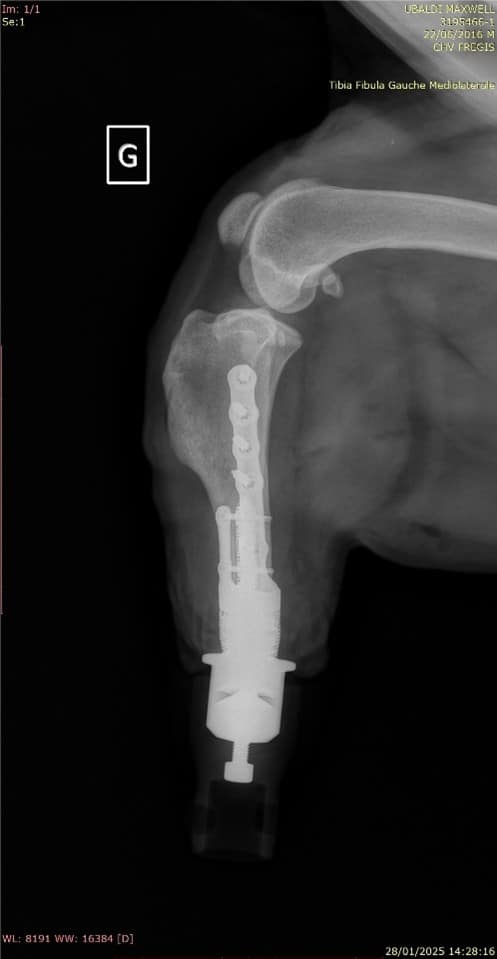

Maxwell est un chien Golden Retriever de 9 ans présenté en consultation d’orthopédie pour une boiterie du membre pelvien gauche évoluant depuis 2 semaines ainsi qu’une tuméfaction du tarse évoluant depuis 8 mois, dans un contexte d’arthrose évoluant depuis plusieurs années sur les autres membres. Il présente comme comorbidité une hypothyroïdie stabilisée médicalement avec de la lévothyroxine. L’examen orthopédique révèle une tuméfaction ferme et inconfortable à la manipulation du tarse gauche en faveur d’un processus tumoral ou dégénératif prioritairement. Le scanner suggère une prolifération d’atténuation tissulaire en périphérie de l’articulation tibio-talienne et les biopsies confirment un processus néoplasique de type sarcome des tissus mous (schwanome plus précisément). La prise en charge thérapeutique de choix a été ici la réalisation d’une prothèse d’amputation.

La prothèse d’amputation est un implant de conception unique intégrant deux parties : une endoprothèse (prothèse qui se fixe dans l’os et traverse la peau) et une exoprothèse (prothèse amovible se fixant sur l’endoprothèse qui permet l’appui).

Chaque exoprothèse est faite sur mesure par des ingénieurs biomédicaux après réalisation d’un scanner afin de s’adapter parfaitement à la taille, au poids et à la démarche naturelle de chaque patient. Au fil du temps, la base en caoutchouc de l’exoprothèse s’use comme la semelle d’une chaussure. Lorsque cela se produit, il suffit de détacher l’exoprothèse de l’endoprothèse et de la remplacer par un pied neuf.

Elle est indiquée seulement pour des lésions distales des membres, à partir du radius distal et du tibia distal. Elle peut être utilisée dans des circonstances de traumatisme, de tumeur ou déformation, dès l’instant que l’os de support de la prothèse est sain (non tumoral et non infecté).